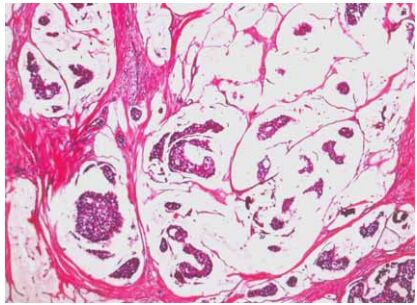

80 一位 65 歲女性於例行健康檢查發現右側乳房有一界線清楚結節,病理檢查如附圖,下列敘述何者正確?

(A)該腫瘤好發於年紀較大的女性,一般來說預後較其他種類的原發性乳房惡性腫瘤差 (B)一般來說都不會有激素接受器(hormone receptor)的表現 (C)該診斷為髓質癌(medullary carcinoma) (D)罹患該腫瘤的病人有 BRCA1 mutation 的機率較罹患其他種類的原發性乳房惡性腫瘤的病人要高